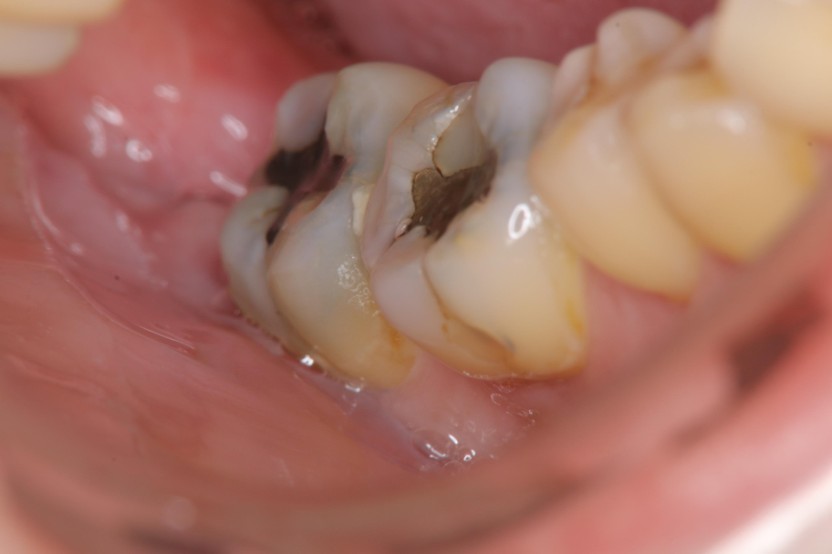

治療前,右下阻生齒造成牙周腫脹